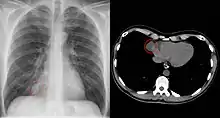

Since pericardial cysts are often asymptomatic, the most common diagnosis is through incidental finding on a chest x-ray.[1][2] When patients have symptoms, transthoracic echocardiogram is one of the first tests used to look for a pericardial cyst.[3] CT or MRI may also be used to diagnose pericardial cysts.[4][5][6] On CT and MRI a pericardial cyst will commonly appear as a round, fluid-filled structure surrounded by thin walls.[4][5][6] Diagnosis of a pericardial cyst can also be made before birth using ultrasound.[2]